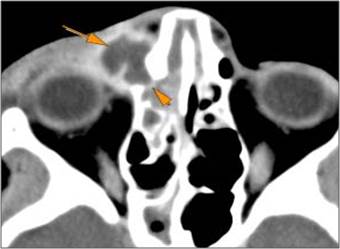

Eyes

Proptosis is present.

The optic nerve has a stretched appearance.

There are signs of a decompressed globe.

There is evident general optic sheath swelling or swelling at the junction of the globe and sheath to suggest an optic sheath hematoma.